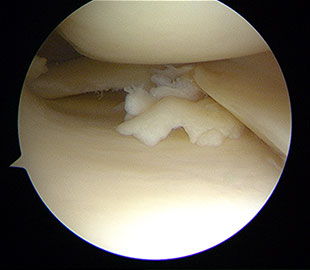

Lässt sich in der bildgebenden Diagnostik keine eindeutige Schädigung an den Menisken nachweisen und bestehen dennoch bei den Patienten eindeutig zu behandelnde Symptome, so sollte eine Gelenkspiegelung durchgeführt werden.